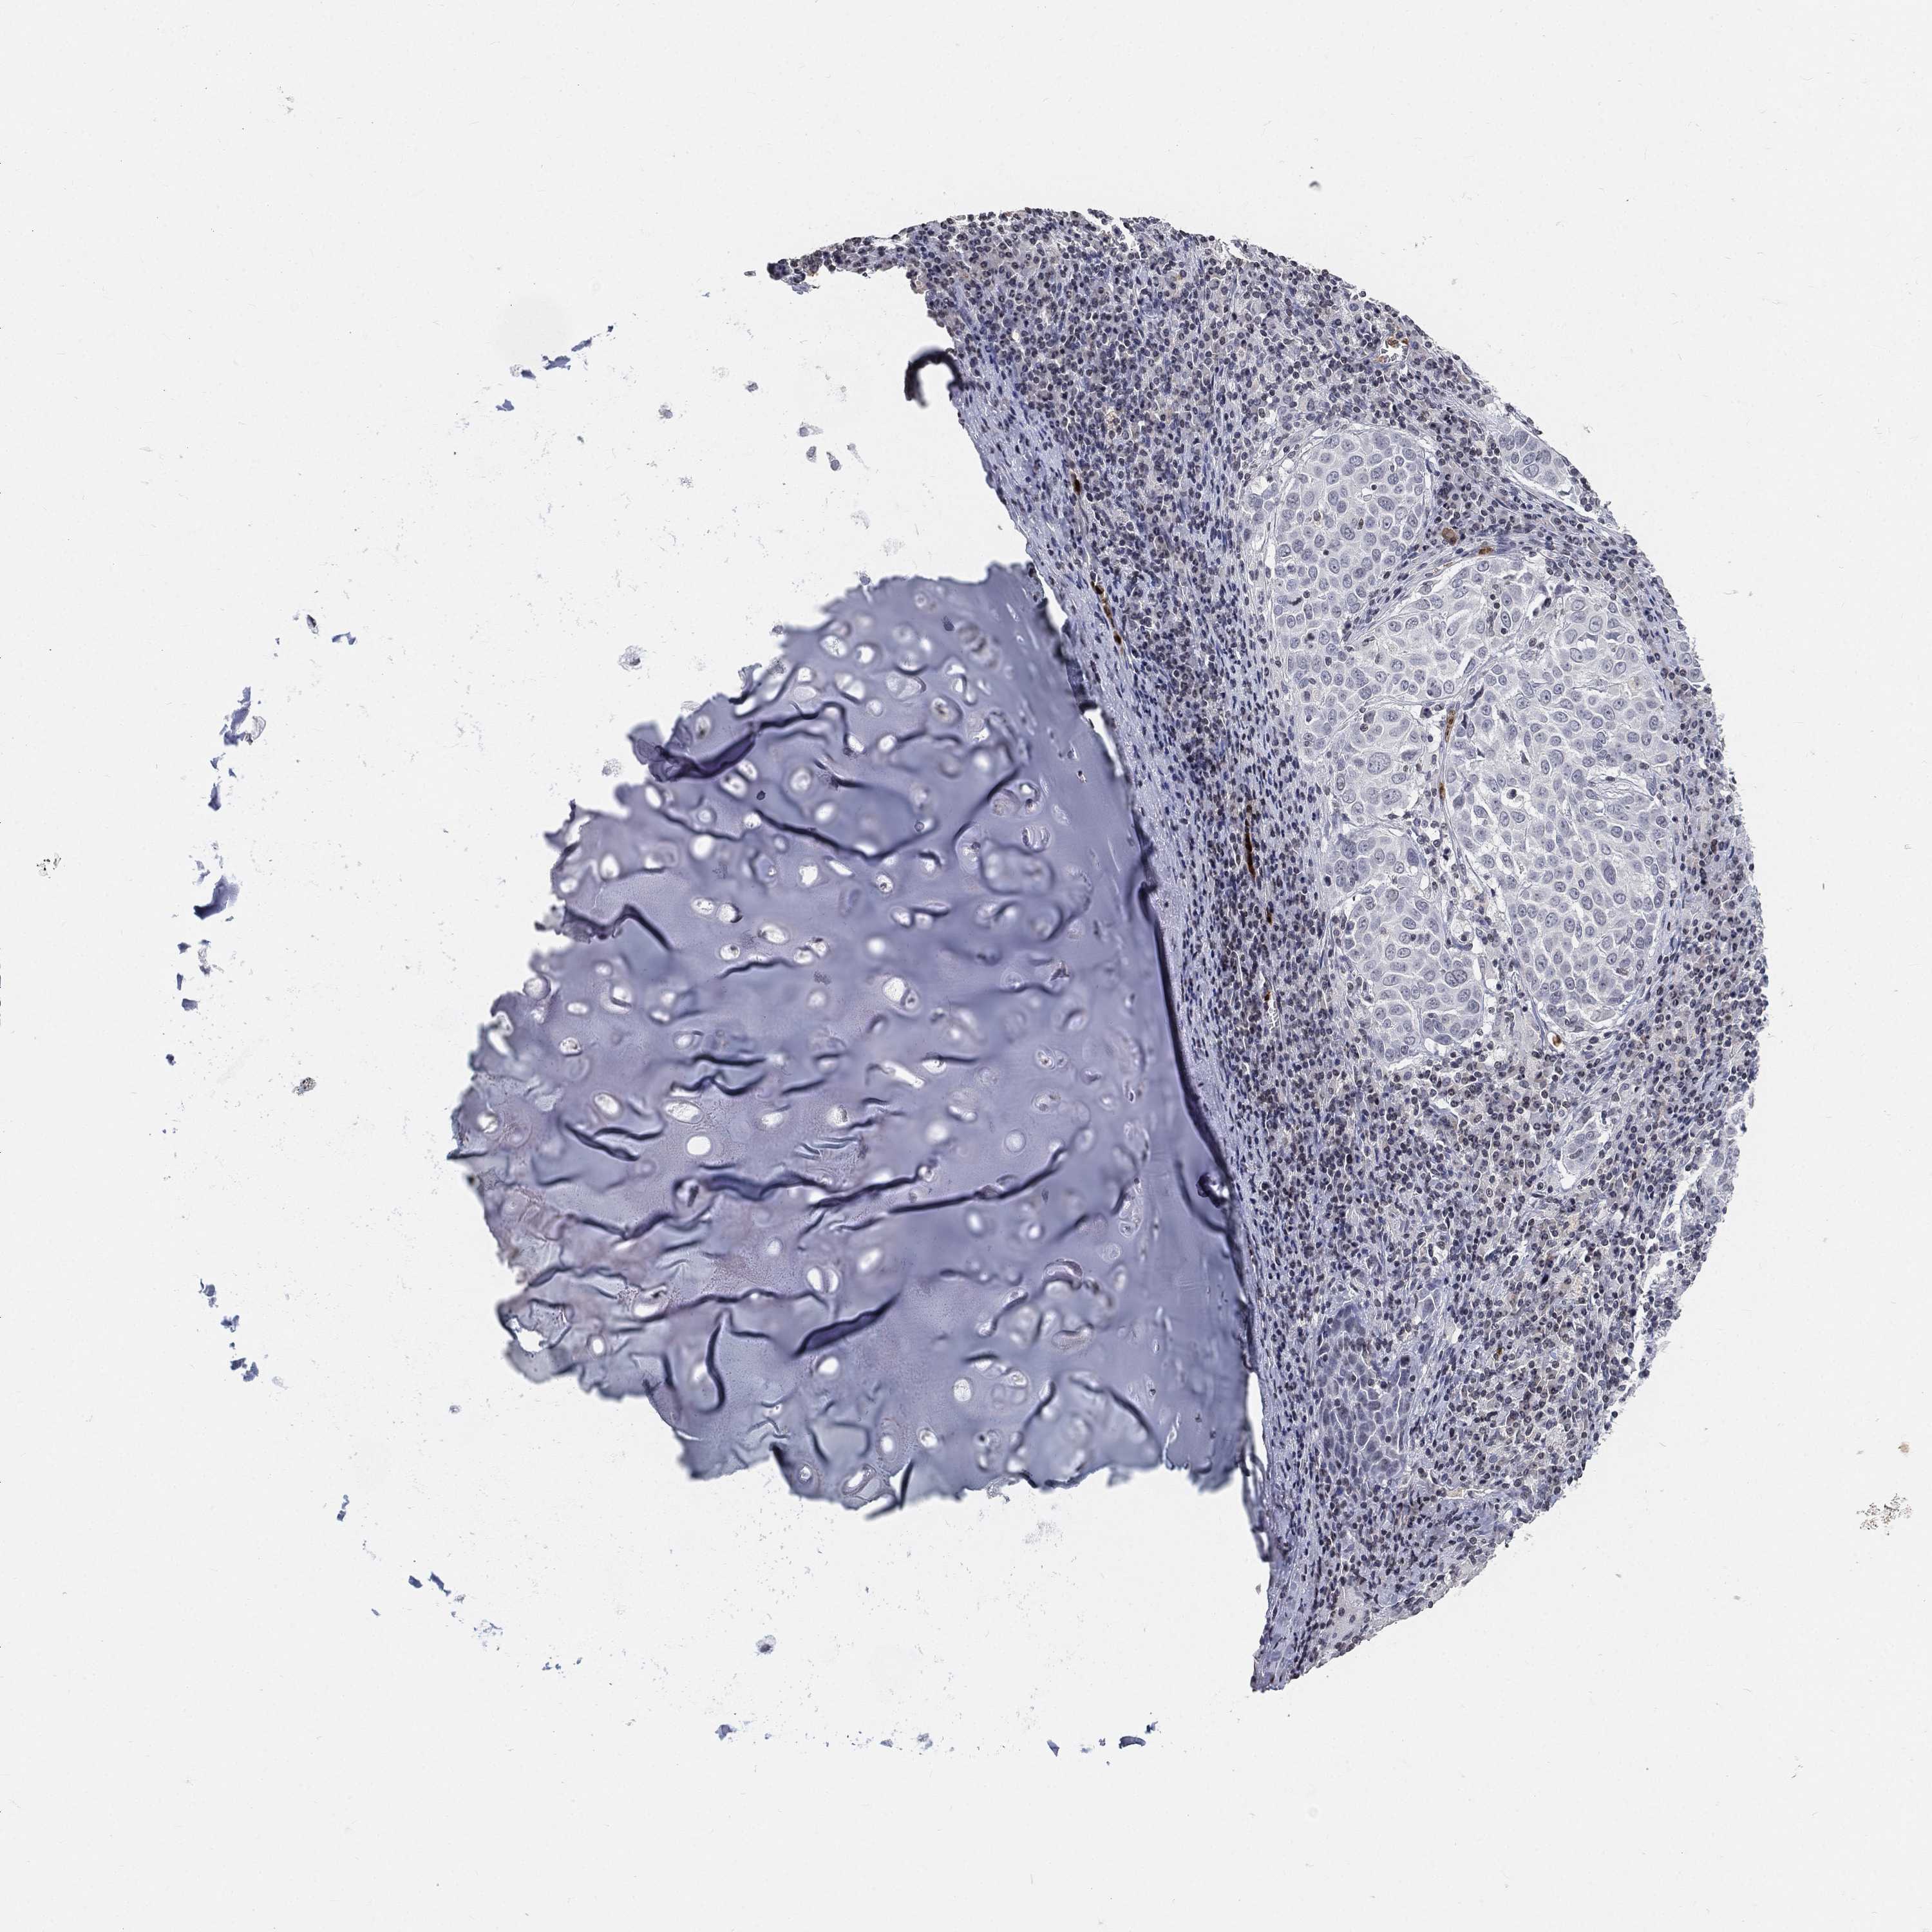

CANCER LUNG CANCER Show tissue menu

LUAD TCGA LUAD VALIDATION LUSC TCGA LUSC VALIDATION PROTEIN LUAD CPTAC PROTEIN LUSC CPTAC PROTEIN EXPRESSION

ANTIBODIES

AND

VALIDATION